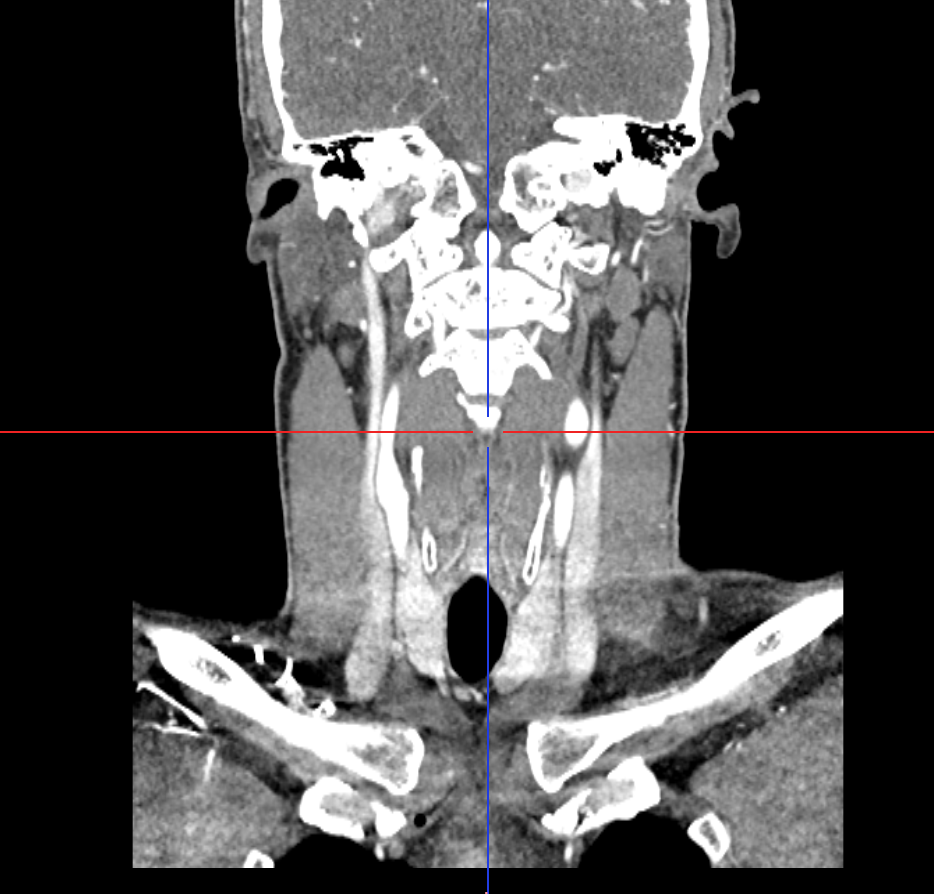

The distance between the styloid processes and the lateral masses of the C1 vertebra is 1.4 mm on the right and 2.2 mm on the left. The styloid processes are symmetrical and measure 25.5 mm in length.

Looked more into the hyoid bone piece that you pointed out @Isaiah_40_31 . It appears that the left greater horn is pressing into or resting on my carotid sinus on that side. Which is a bit alarming because of it’s role in blood pressure regulation and where vagus, and other nerves pass by. I’ve been to the ER a few times during this journey and all times my throat bone was at it’s sorest. My blood pressure was 155/106 upon admission and I wasn’t panicked or had any cognitive-driven anxiety, but definitely felt off. I wonder if the styloids/scm are culprits for pressure headaches, eye pain, tinnitis and dizziness, while the left greater horn is causing also dizziness/vertigo and vagus nerve and baroreceptor stuff (i.e., acid reflux, blood pressure and HR fluctuations, etc.)?

Then I found this lovely forum, where members seem to have a higher IQ (I actually test IQ frequently as a psychology student lol) than most of the doctors I’ve interacted with. You all have helped me narrow down my concerns and what things to hone in on – that being my styloids, hyoid, carotids, and jugulars. Based on our collective thoughts and what makes sense for what I’m experiencing, it appears that both IJVs are, to some degree, being compressed between my styloids and C1. It also appears that the left greater horn of my hyoid bone is pressed up against the area of my carotid sinus. I think a combination of these are contributing to my symptoms. We know IJV compression can cause some nasty symptoms, and I know based on research that pressure or irritation to the area of the carotid sinus can cause dizziness, weakness, and other pre-syncope symptoms that I experience with head movements and swallowing.